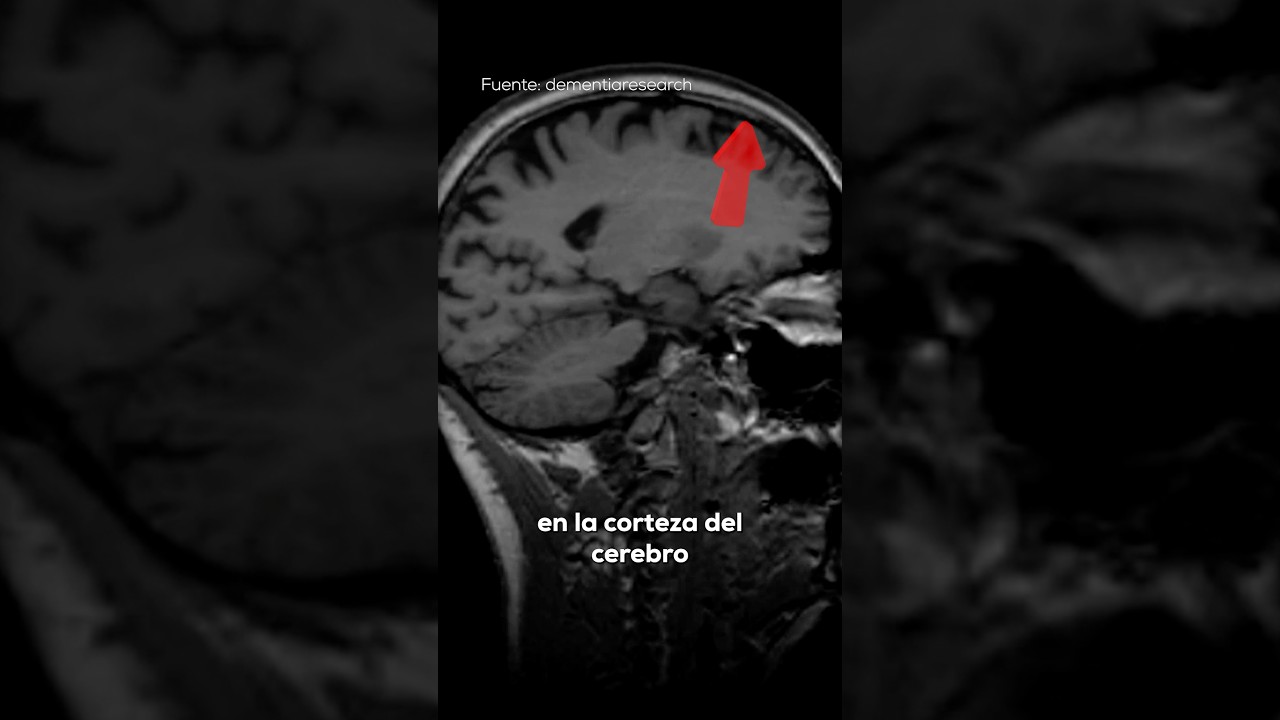

Las técnicas de imagen, como la resonancia magnética (RM), son herramientas clave para visualizar la atrofia en el cerebro. Estas imágenes permiten a los médicos observar cambios en el volumen cerebral y detectar áreas de atrofia. La RM es particularmente útil porque no utiliza radiación y proporciona imágenes detalladas de las estructuras cerebrales.

La atrofia cortico subcortical se refiere a la reducción del volumen de áreas específicas del cerebro, que incluyen tanto la corteza cerebral como las estructuras subcorticales. Estas áreas son esenciales para una variedad de funciones cognitivas, desde la memoria hasta el control motor. La atrofia puede ser un proceso normal del envejecimiento, pero también puede ser un signo de condiciones neurodegenerativas.

La corteza cerebral es la capa externa del cerebro, responsable de funciones complejas como el pensamiento, la percepción y la toma de decisiones. Por otro lado, las estructuras subcorticales, que incluyen el tálamo y los ganglios basales, juegan un papel crucial en la regulación del movimiento y en el procesamiento de la información sensorial. La atrofia en estas áreas puede llevar a una serie de problemas, desde dificultades en la memoria hasta alteraciones en la coordinación motora.